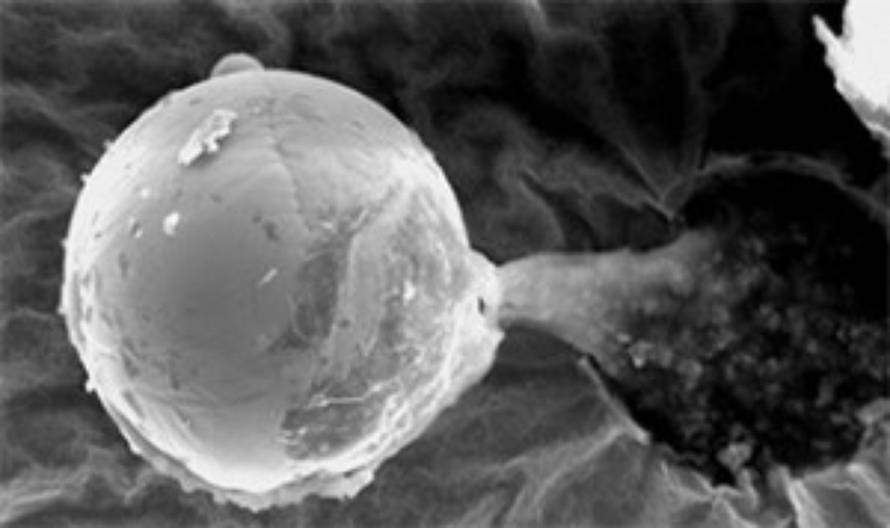

Profesor Milton Wainwright sa Sveučilišta u Buckinghamu kaže da je rendgenska snimka otkrila kako se u misterioznoj kugli nalazi ljepljiva biološka tekućina